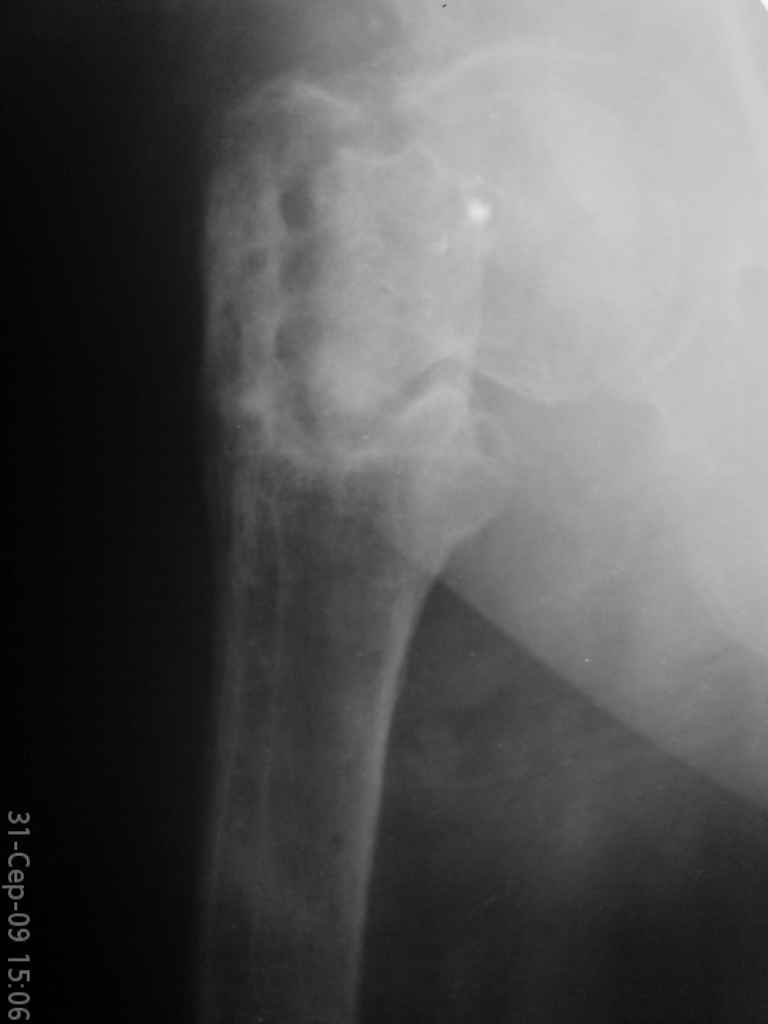

Больная, 62 года,жалуется на боли,неопорность левой ноги. Ходит с помощью костылей, укорочение ноги 3 см. Два года назад была оперирована кокой-то накостной пластиной, пластину удалили 4 мес назад. Вопрос такой: предлагать эндопротезирование или делать МОС (что-то по типу стержня Gamma)?

За качество снимков извините, по данным МРТ - головка живая